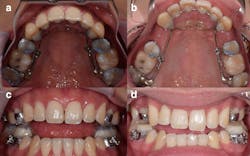

What she said happened next was ghastly. Kragulj alleged in her lawsuit that instead of changing her jaw, the device pushed her teeth forward through the bone that anchors their roots in place, which put her front teeth in jeopardy. Dozens of photos provided by her attorney show that over time her teeth bulged out of her mouth, warping her smile into a twisted mess. In the three years since filing her suit, Kragulj has had four unsalvageable teeth removed and two others ground to nubs, she said.

Dentists across the country promote the AGGA on their websites, often claiming it can “grow,” “remodel,” or “expand” an adult’s jaw without surgery, sometimes saying it has the potential to make patients more attractive and treat common ailments like sleep apnea and TMJ. However, after reviewing dental scans that the AGGA inventor submitted in court to prove the device works, eight experts told KHN and CBS News the scans show signs of the AGGA displacing teeth instead of expanding the jaw. Some experts said, based on their experience with former AGGA patients, the device caused tens of thousands of dollars in damage to the patient’s mouths.

However, in a series of interviews with orthodontists, periodontists, and maxillofacial surgeons — all of whom have more training than the average dentist — these experts said that while it is possible to expand the jaws of children without surgery, jawbones stop growing forward as people mature into adulthood. Experts who have examined patients fitted with an AGGA said the device aggressively moved teeth, sometimes creating an illusion of jaw growth by tilting some teeth forward and forcing gaps between others. In the worst cases, those experts have seen teeth shoved so far out of position that their roots are pushed free of the bone and into the gums.

Dr. George Mandelaris, a Chicago-area periodontist and member of the American Academy of Periodontology Board of Trustees, said Galella’s dental scans show “harm” to the bone that holds teeth in place. Mandelaris said he has consulted with 11 AGGA patients, including Kragulj, who looked as if “a bomb went off in her mouth.”